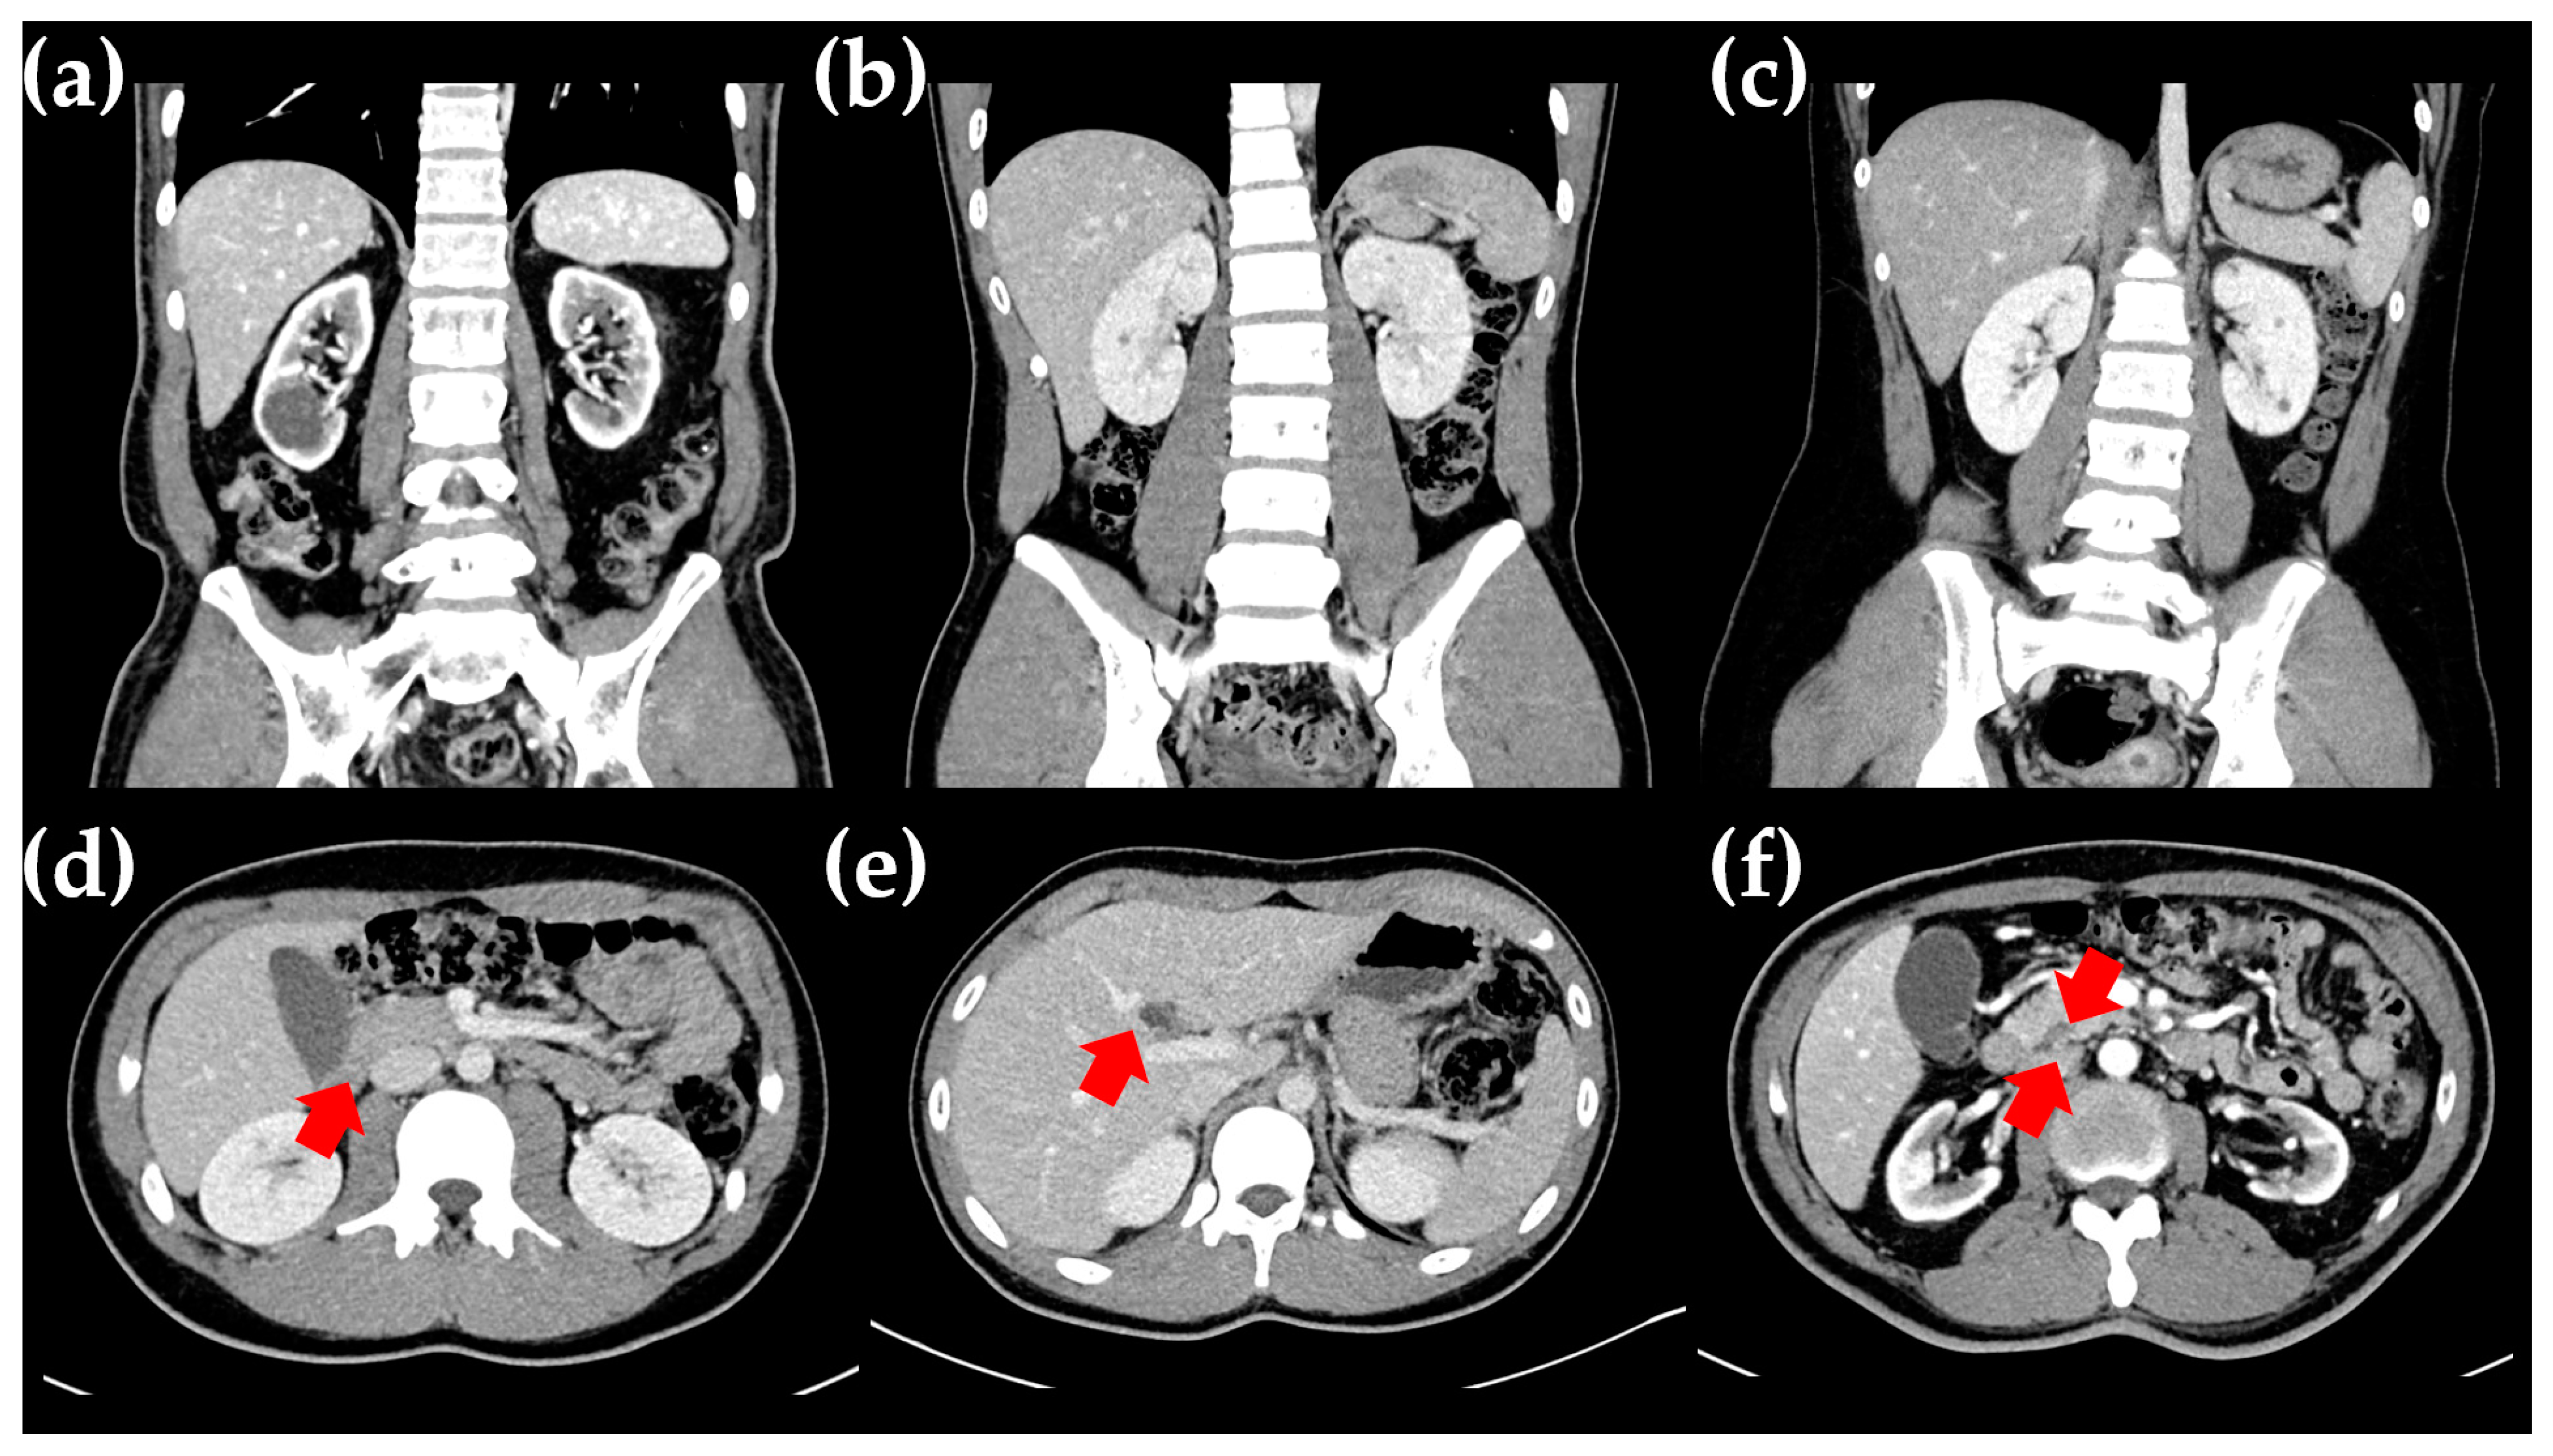

2.1. The Proband

2.2. The Proband’s Father